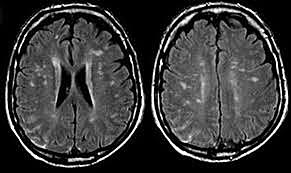

• Lobotomía

Lobotomía

Es una psicocirugía que consiste en el corte de fibras nerviosas del cerebro cuyo procedimiento más común es la introducción de una herramienta punzante para alcanzar el lóbulo frontal del cerebro a través de la cavidad del ojo.